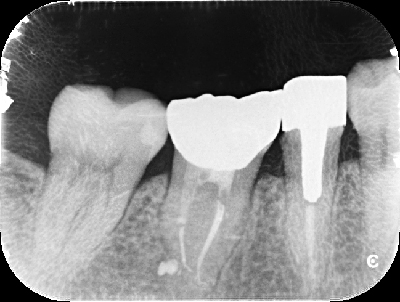

上記は歯のレントゲン写真です。二本足のように、歯が歯茎に埋まってますが、右の歯の黒い部分(二本足のつけ根の部分)が菌に冒されてます。

-

非常に細かい部分ですが、顕微鏡を使い、菌に犯されているところを治療した後にレントゲンを取りました。

しっかり治ってます!!